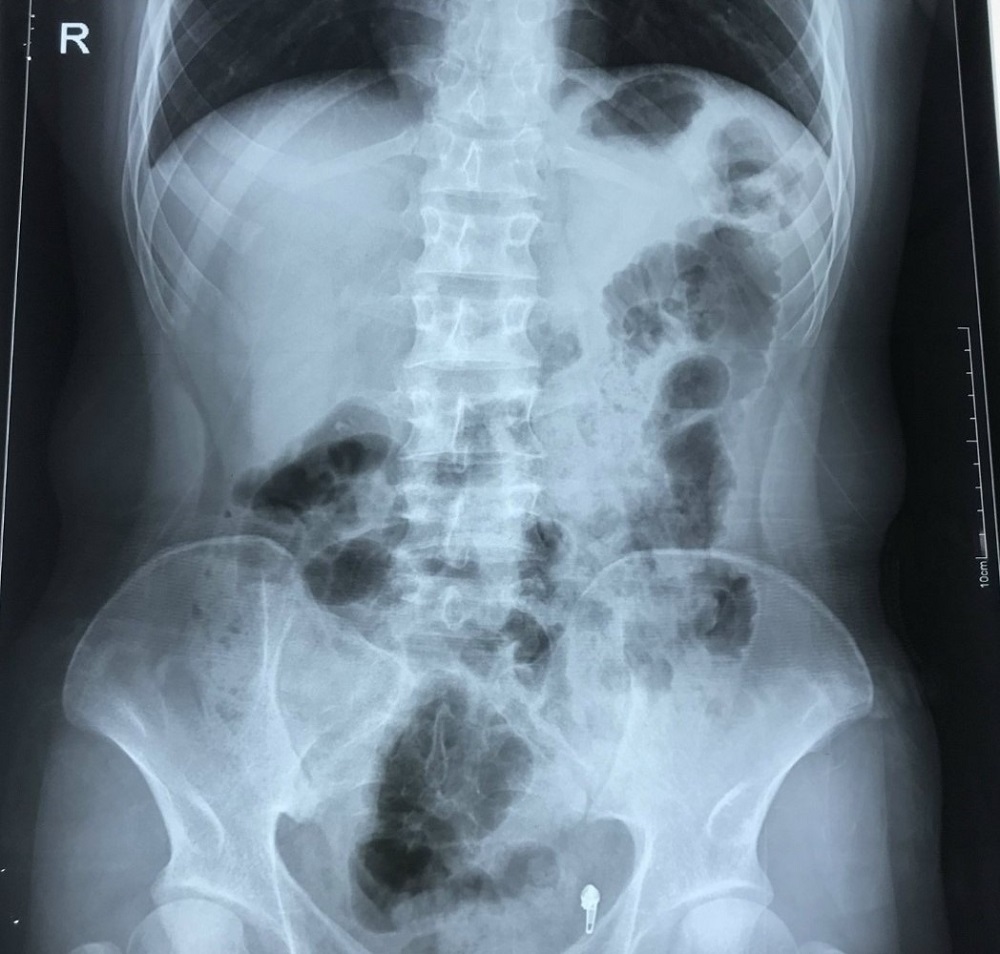

| Phim chụp X-quang của bệnh nhân cho thấy tình trạng phủ tạng đảo ngược với trái tim nằm bên lồng ngực phải. Ảnh: BVCC |

Tuy nhiên, có một điều khiến các bác sĩ rất bất ngờ là trái tim bệnh nhân H. nằm bên lồng ngực phải, ở vị trí đảo ngược so với người bình thường.

Đảo ngược phủ tạng là tình trạng bẩm sinh, trong đó các cơ quan nội tạng trong ngực, bụng bị đảo ngược, phản chiếu theo mặt phẳng đứng dọc so với vị trí bình thường. Các phủ tạng có thể bị đảo ngược hoàn toàn hoặc chỉ một vài cơ quan đơn thuần.

Đây là một dạng dị tật có tính di truyền gen lặn tương đối hiếm gặp, với tỷ lệ 1/10.000 dân, trong đó có khoảng 5-10% có dị tật tim bẩm sinh, còn lại có cuộc sống bình thường, không ảnh hưởng đến sức khỏe.